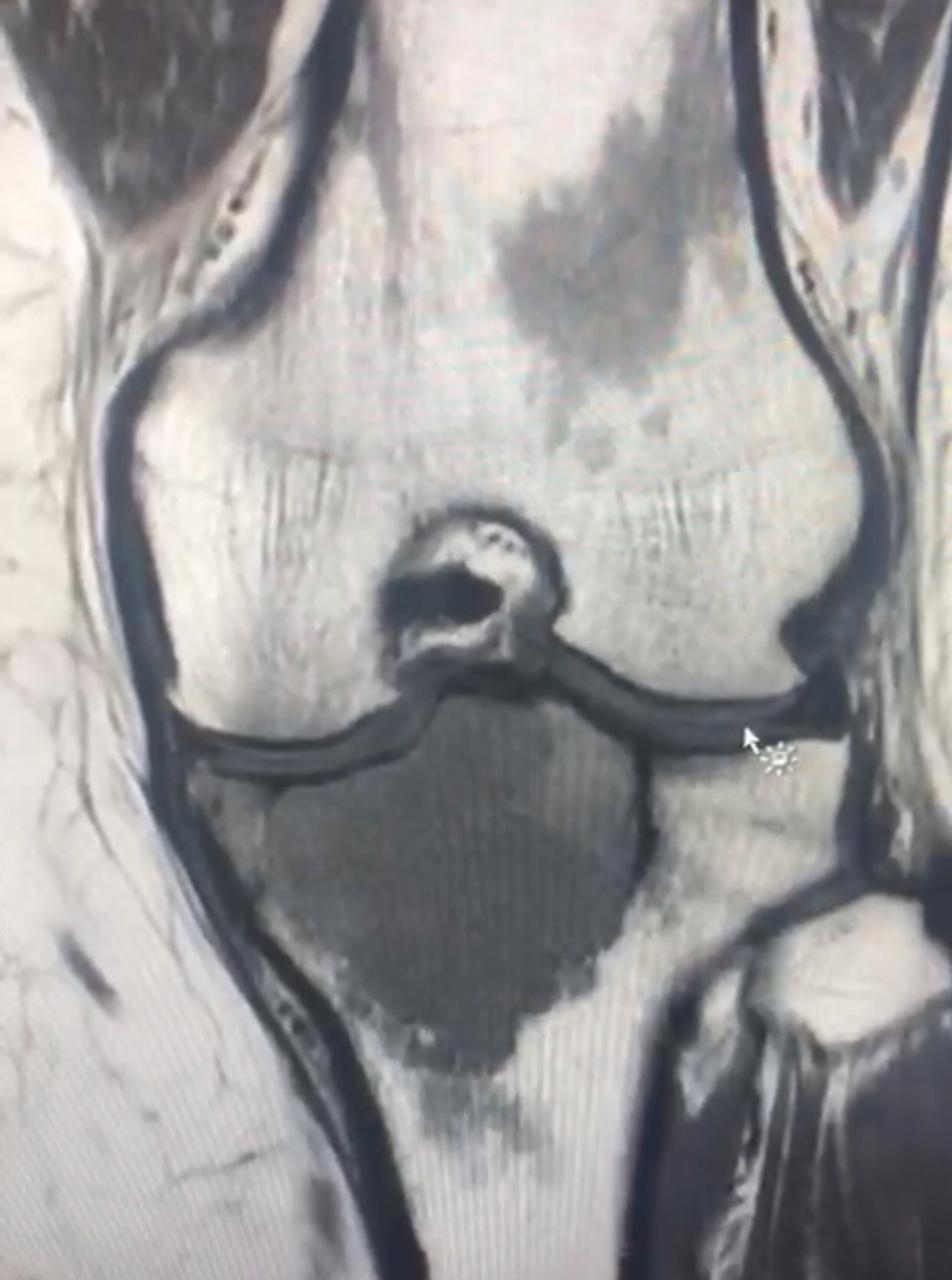

يواصل الفريق الطبي المختص في جراحة أورام العظام والعضلات في مستشفى المدينة المنورة إجراء العمليات الجراحية التخصصية في هذا المجال ، حيث نجح الفريق مؤخراً في استئصال ورم في أعلى عظمة الساق اليسرى لمريضة.